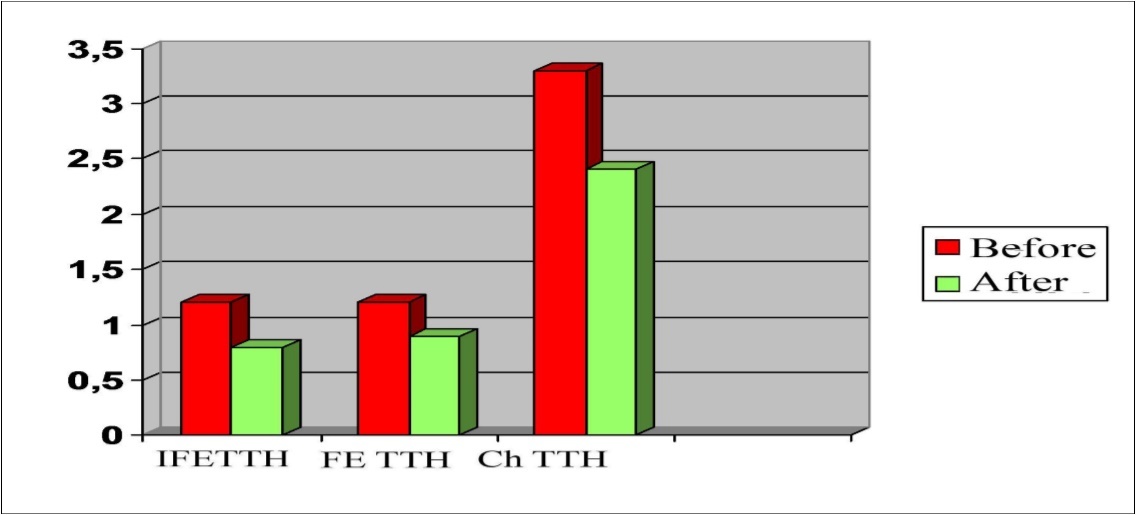

In all clinical groups, the Visual Analogue Scale (VAS) headache intensity indices gradually decreased from 3.1±1.1 points to 1.8±0.7 points in the group of IFE TTH, from 3.5±1.4 points to 1.9±1.1 points in the group of FETTH and from 7.3±2.1 points to 5.2±1.7 points in the group of ChTTH (Figure 6). As can be seen from the figure, the headache intensity in all groups decreased statistically insignificantly.

Figure 6.Dynamics of headache intensity frequency in a patients with TTH during treatment with Phenibut

The dynamics of pain in the pericranial muscles before and after treatment is presented in Figure 7. As can be seen from figure, according to the visual analogue scale (VAS) , the degree of pain in the pericranial muscles decreased in all clinical groups, however, the minimal statistical significance (P<0,05) was observed only in patients with chronic TTH (from 3.3±0.3 points to 2.4±0.2 points).

Figure 7.Dynamics of indicators of pericranial soreness muscles in a patients with TTH during treatment with Phenibut